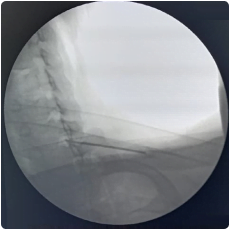

Intraop fluoroscopy image of needle placement at the cervical facet